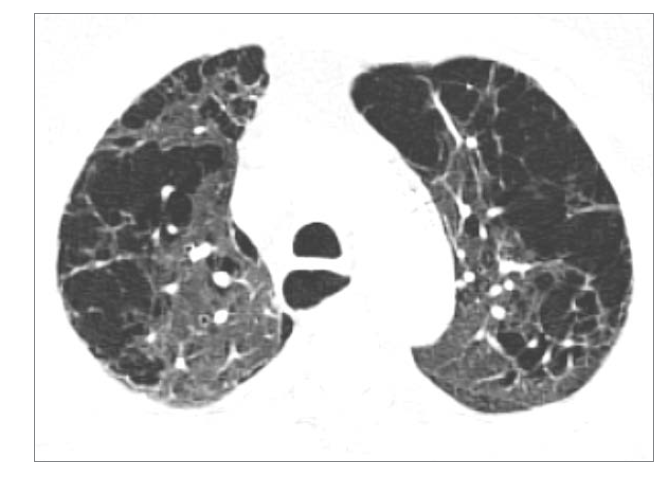

What is this?

Panlobular emphysema